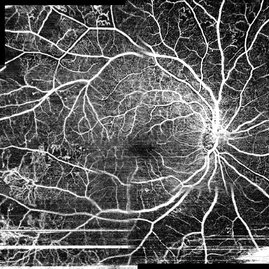

Matrix fundus photography of 52-year-old woman with proliferative diabetic retinopathy on her both eyes. She had a diabetic gistory for 19 years. Doctor suggests her to have a vitrectomy on her right eye (poor prognosis).

Photographer: Yohanes Harry Purwanto, Klinik Mata Nusantara

Imaging device: Topcon TRC 50 DX Type IA

Condition/keywords: fundus photograph, proliferative diabetic retinopathy (PDR)